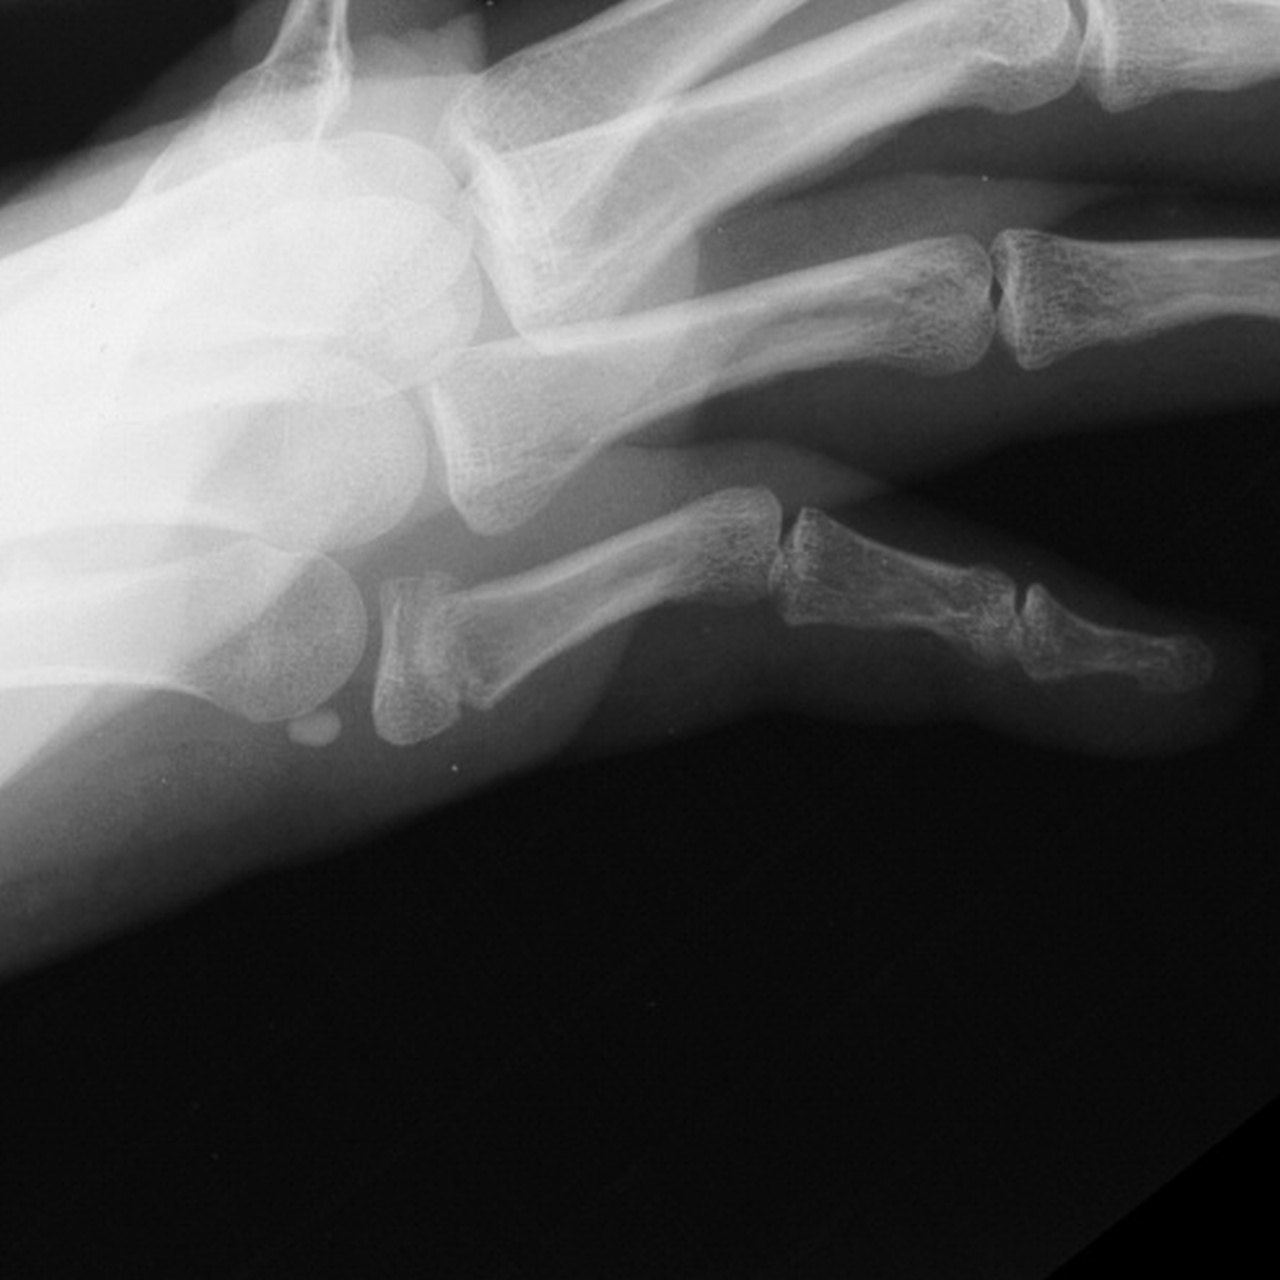

Case 1.

A malaligned three

week old fracture. Notice the

typical zig zag collapse pattern resulting in flexion

of the proximal interphalangeal

joint to the same degree as the fracture angulation. |